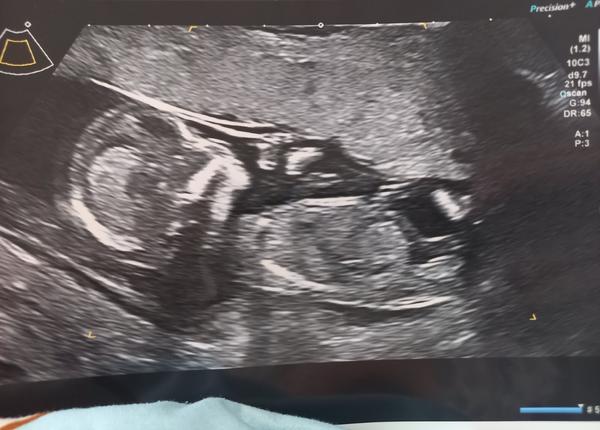

Poznáme pohlaví dítěte ze snímku ultrazvuku?

@lori1097 tak to moc gratuluji, hlavně ať jste oba zdraví😊 no mě to čeká konec června, začátek července, za chvíli to uteče a bude nás také o jednoho člena více😊 já i přítel bychom chtěli chlapečka. Na prvním screeningu nám řekli, že to vypadá na chlapce, ale není si jistá no a od té doby už nevím nic, byla jsem 3x na ultrazvuku a nechtělo se vůbec ukázat 😌 prý se holky spíš nechtějí ukazovat, tak snad. Modlíme se už od začátku za chlapečka😂 Na další ultrazvuk jdu až za měsíc. Jsem tak zvědavá, že si i čtu na internetu babske rady atd, abych se trochu uklidnila😂

@karolina226 Ahoj, podle mě kluk. My měli holčičku a hrbolek byl víc rovně 🙂